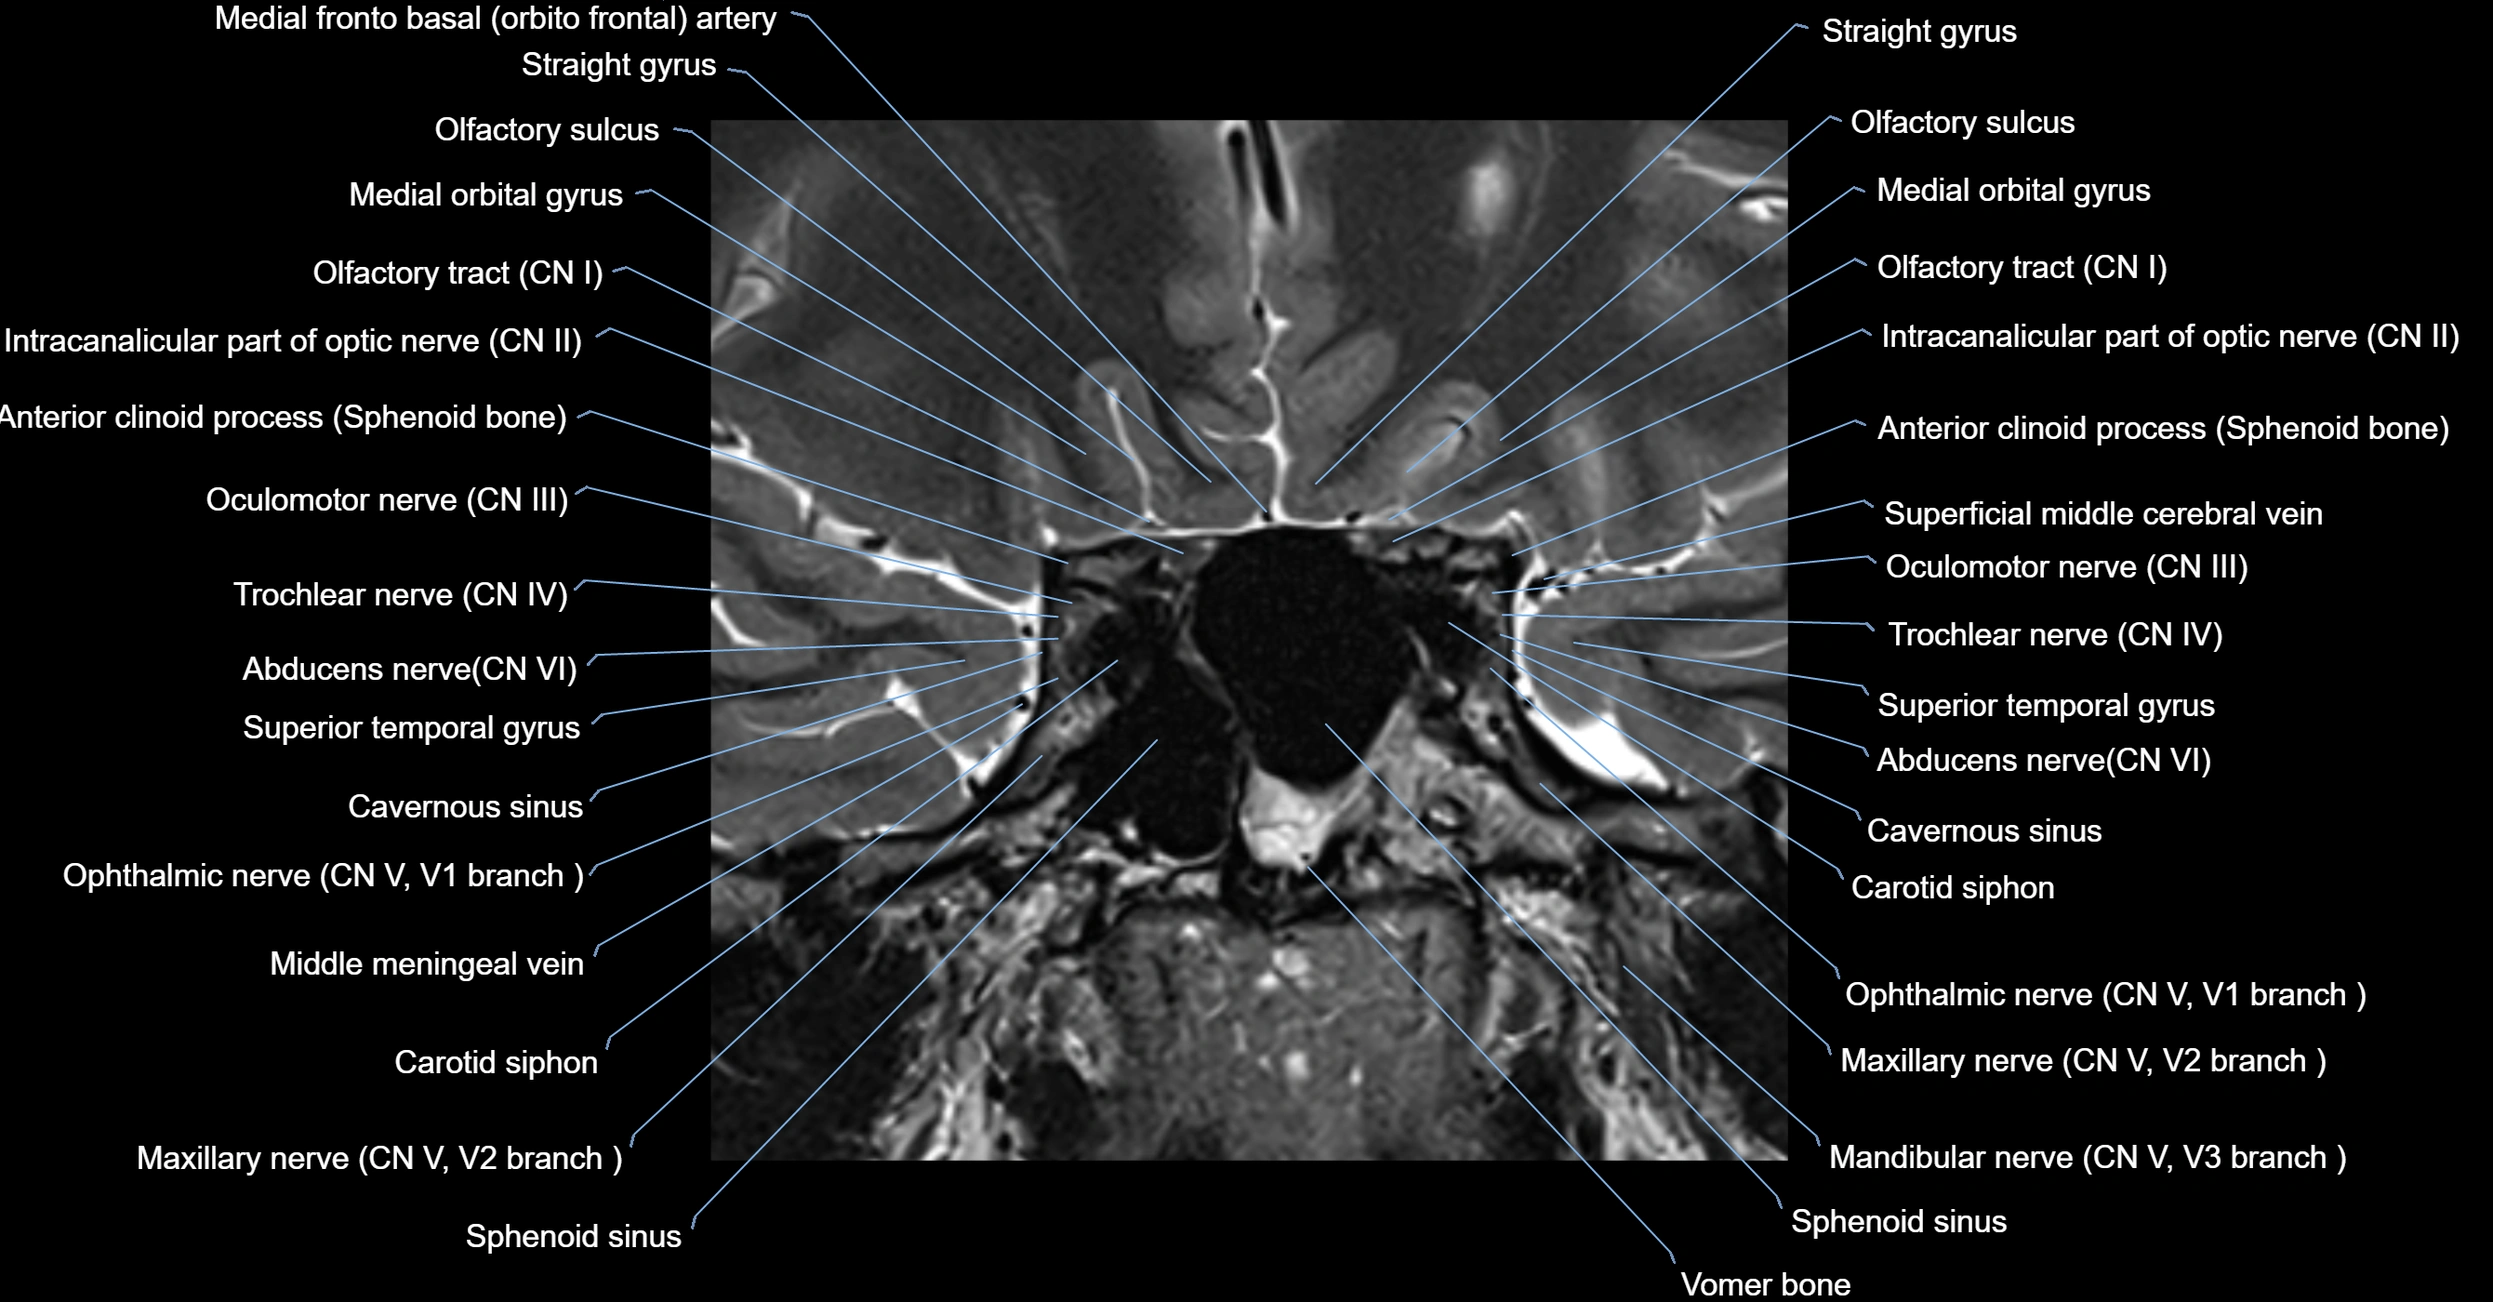

MRI Appearance

-

The abducens nerve is a small, thin, linear structure

Best visualized on high-resolution T2-weighted 3D MRI sequences (e.g., FIESTA or CISS)

Seen as a hypointense (dark) line running from the brainstem at the pontomedullary junction, traversing the prepontine cistern, and entering Dorello’s canal under the petrosphenoidal ligament, then into the cavernous sinus, and finally the orbit

May be challenging to visualize in standard MRI due to its small size

Pathology may be inferred by absence, displacement, or enhancement of the nerve

MRI images